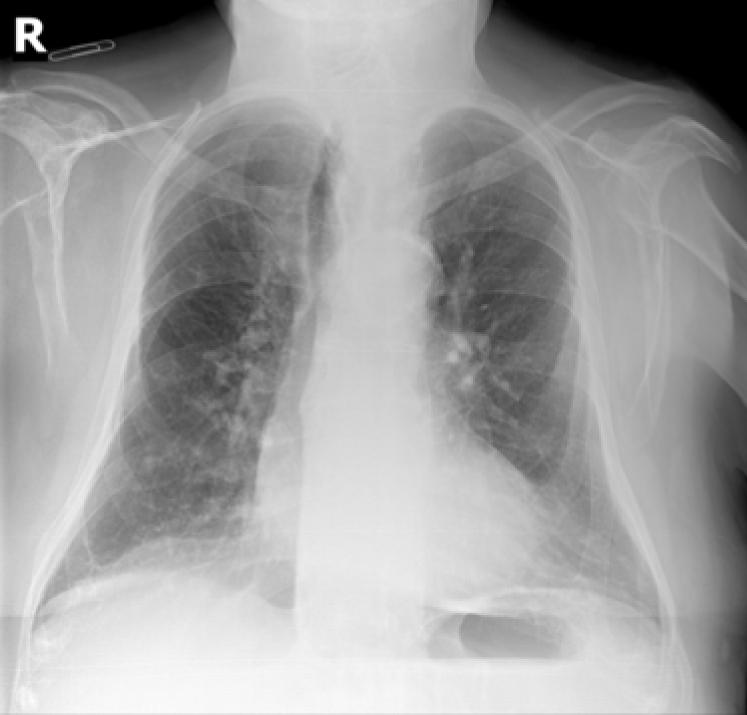

4.3 Image projections and additional characteristics

The mean and standard deviation images were obtained for visualization purposes. They were calculated from a random sample of 500 training examples.

These images showed relevant differences among the different x-ray projections (see Fig. 17). In PA, the mean shows that images were fairly aligned to the center, while the standard deviation for the same random sample of 500 images, in which higher values are whiter, indicates a higher variation at the boundaries when compared to the center. In AP supine position, the mean heart silhouette was enlarged. Vertical and horizontal lines in the pediatrics standard deviation illustrate that there are many sizes of frames enclosing the chest and part of the abdomen.

Refer to caption

(a) P-A

(b) Lateral

(c) AP supine

(d) AP erect

(e) Ribs

(f) Pediatric

(g) P-A

(h) Lateral

(i) AP supine

(j) AP erect

(k) Ribs

(l) Pediatric

Figure 17: From a) to f): Mean image by position view. From g) to l): Standard deviation image by position view.